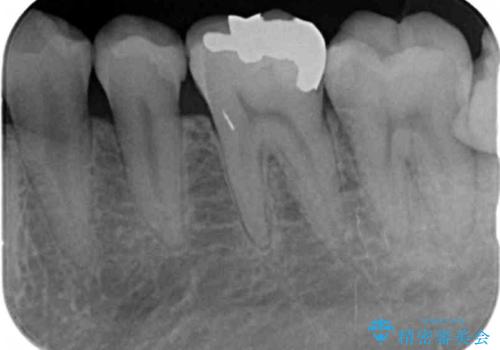

- 長年気になっていた銀歯を白く、自然にしたいと希望され来院されました。

銀歯を丁寧に除去し、内部に虫歯の再発がないかどうか拡大鏡下で確認した上で、精密に封鎖することのできるセラミックインレー治療を計画します。